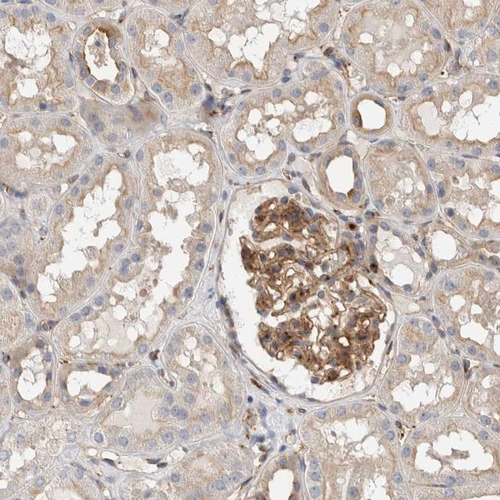

Immunohistochemical staining of human lymph node shows strong cytoplasmic positivity in non-germinal center cells.